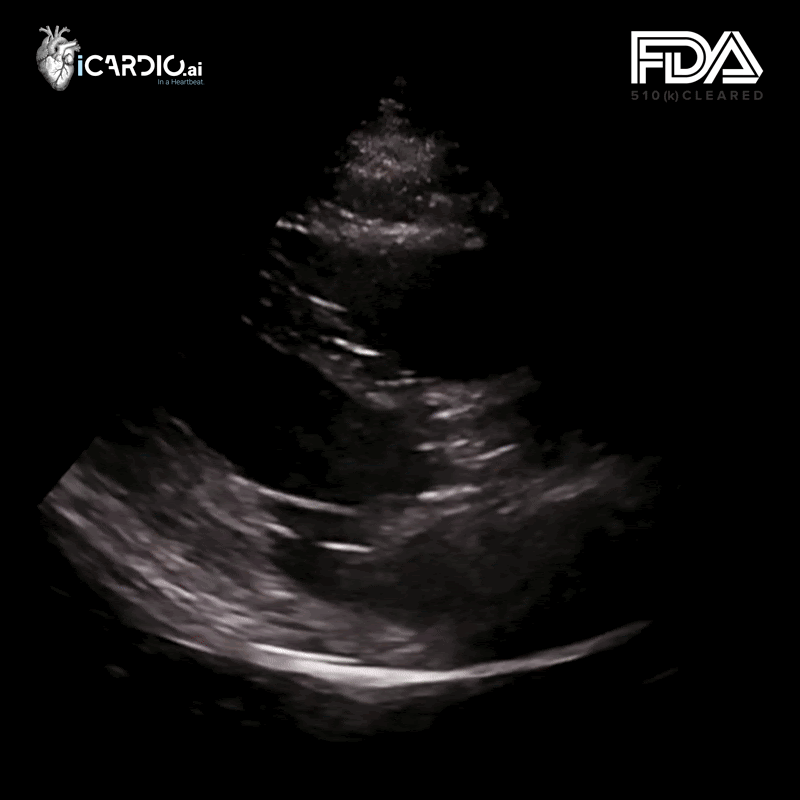

iCardio.ai CardioVision™ is an FDA-cleared AI software indicated as a diagnostic aid to support the detection of Aortic Stenosis. Taking in only a parasternal long axis (PLAX) clip, iCardio.ai CardioVision™ is used during a diagnostic workup to determine the likelihood of clinically significant aortic stenosis. The algorithm uses deep learning to predict aortic stenosis without explicitly measuring any variable, relying on deep learning. (Wessler, Benjamin S., et al. "Automated detection of aortic stenosis using machine learning." Journal of the American Society of Echocardiography 36.4 (2023): 411-420.)